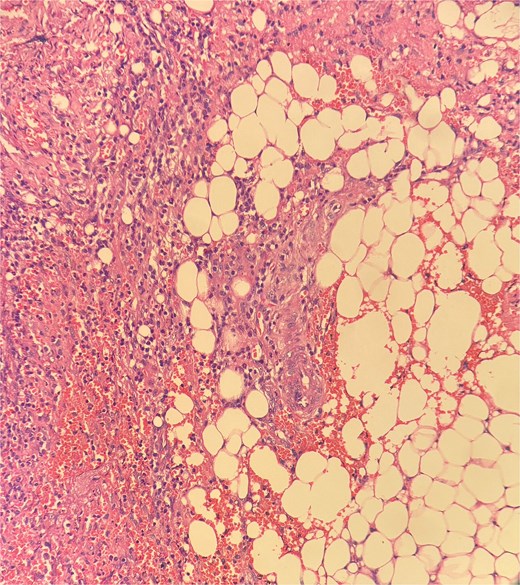

Sections show a dense inflammatory infiltrate within the subcutaneous adipose tissue, consistent with panniculitis. The infiltrate is composed of neutrophils, lymphocytes, plasma cells, and histiocytes.

Histopathological examination showed ghost-like adipocytes and foamy histiocytes.